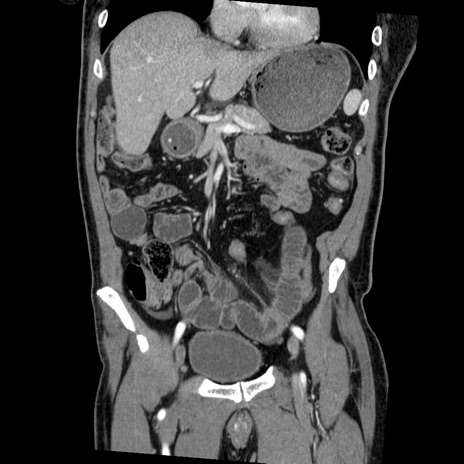

症例22(冠状断像)

【症例】50歳代男性

【主訴】腹痛

【現病歴】AVMからの被殻出血のため回復期リハ病棟入院中。 本日午後3時頃急に下腹部痛が出現した。

【既往歴】AVM、被殻出血、虫垂炎、高血圧

【身体所見】意識晴明、左半身不全麻痺、会話の理解は良好、36.5°C、腹部:膨隆、全体に板状硬、下腹部正中に圧痛点あり、反跳痛-、筋性防御不明、右下腹部にope scar

【データ】WBC 9400、CRP 0.06